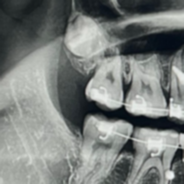

내 상악의 사랑니는 진짜 유별나다. 치아 뿌리와 머리 위치가 바뀐 역위 사랑니이며 완전 매복이었다. 그리고 위치가 너무 높아서 거의 광대뼈에 달린 수준이었다. 그냥 하나만 해도 어려운데 희한하다… 엄마는… 니는 사랑니도 별나다며… 저기요 누가 낳았는데요…

사실 이런 사랑니는 안 뽑아도 된다. 너무 깊게 박혀있어서 잇몸 밖으로 나올 일도 없고 그냥 반려사랑니로 덮어둬야 하는 게 맞다. 사랑니의 존재는 20대 후반에 알았는데, 그 어느 치과에서도 빼라는 소리를 안 했다.

치아 사진 찍고 나서 역시나 발치가 어려운 케이스라 하셨다. (놀랍지도 않아) 하지만 교정 때문에 뽑아야 하는 거 아니냐며. 례. 맞지요. 한번 해보신 댔다. 중요한 건 “뽑을 수 있어요”가 아니라 “한번 해보죠”라는 거… 엄청난 차이^^ 잇몸 열어보고 다시 덮고 나올 수도 있다고 하셨다^^;; 너무 무서워서 집에 가야 하나 생각하면서 멍 때리는데 선생님이 마취 가글을 내미셨고, 나도 그냥 해보자라는 생각으로 마취를 했다. 의사 선생님은 내 사랑니를 뽑으면 정말 명의가 될 거 같다 말하셨고 나는 이때 제일 도망치고 싶었다.

일어나서 보니 신기한 게 치아를 쪼개지도 않고 통으로 뽑으셨다. 의사쌤 너무 뿌듯해하시고… 명의 된 거냐며… 나 약간 감동했다. 누운 채로 발박수 칠 뻔. 암튼 간호사쌤들도 뽑혀서 다행이라며… 치아 사진 찍어서 보여주셨는데, 그냥 그냥 갓벽하시고 대한민국 최고의 사랑니 명의셔요. 하지만 사랑니 위치가 너무 높아서 코와 입 사이 천공이 생긴 건 어쩔 수가 없었다. 그래도 회복을 잘하면 된다 하셨다.